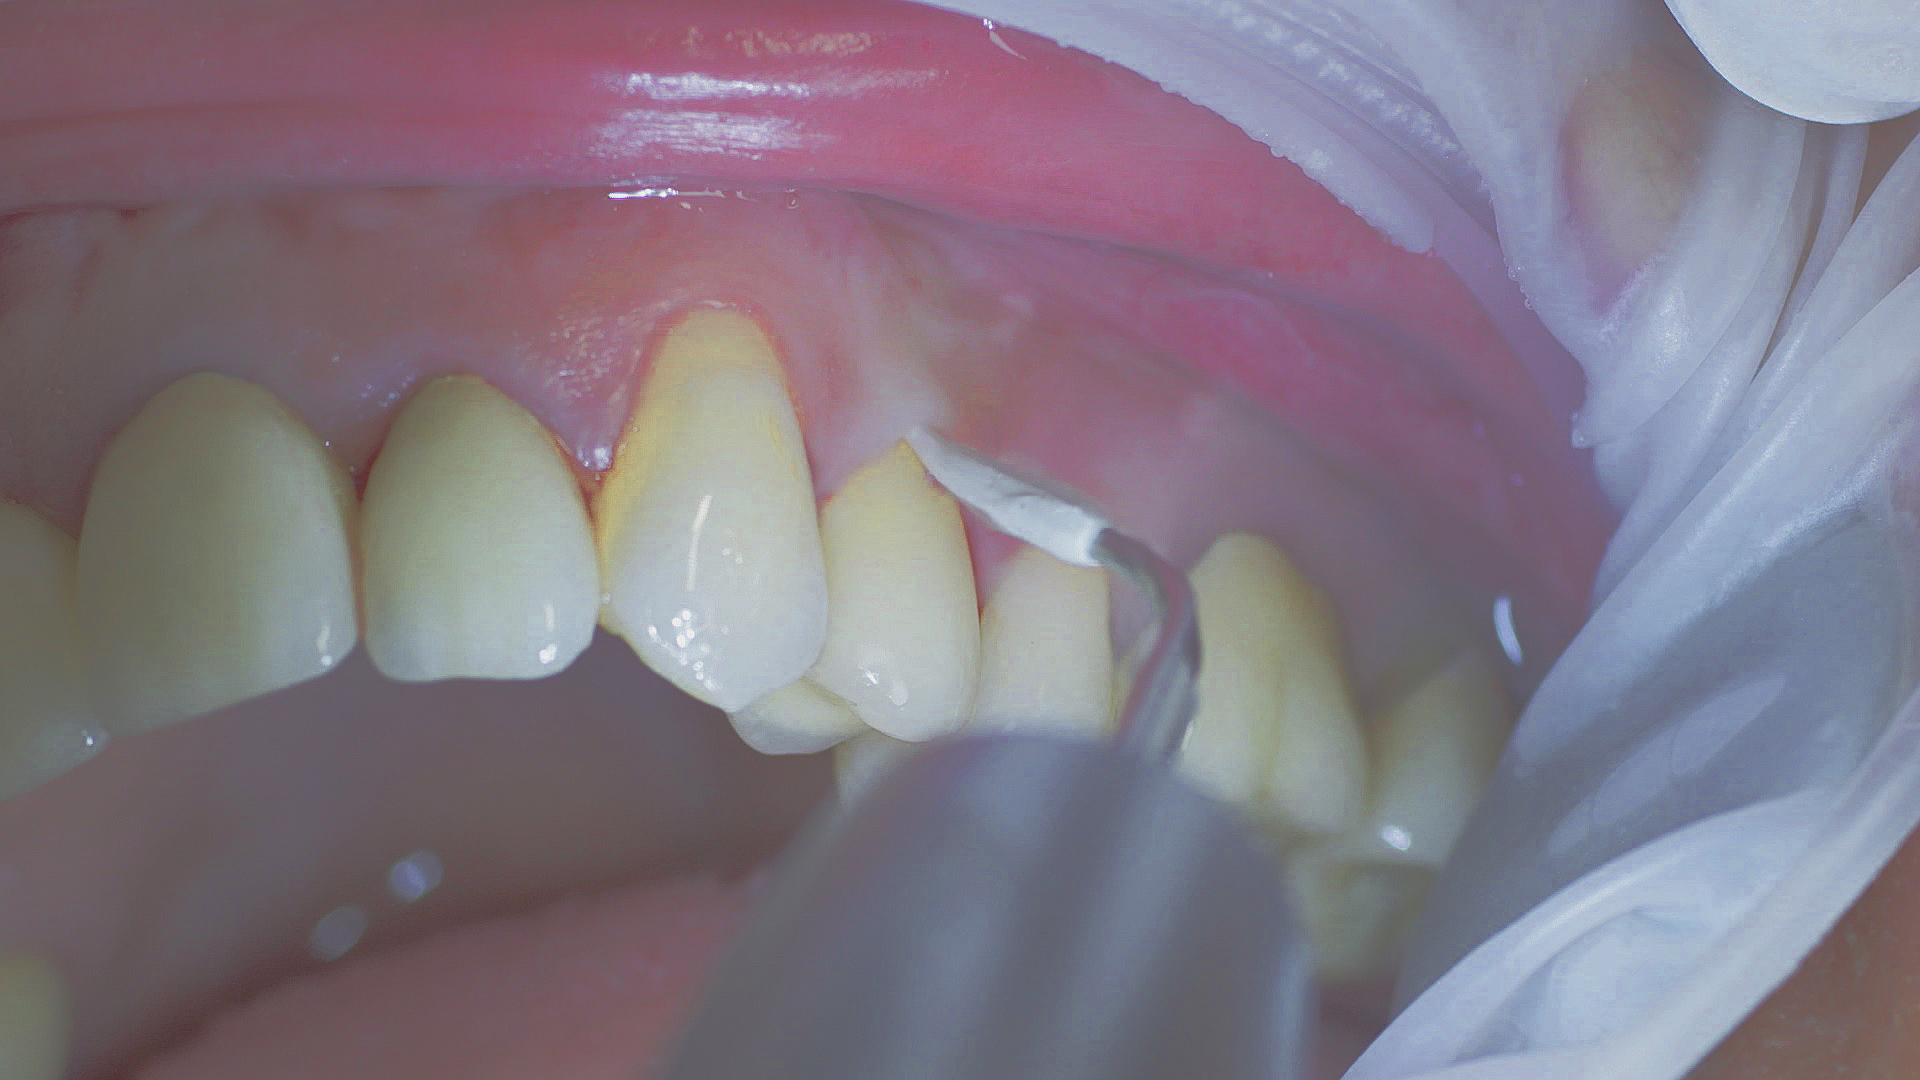

Healthy peri-implant tissue does not show any signs of redness, swelling or bleeding, neither does it secrete pus when probed.[5] Based on the consensus document, Prof. Giovanni Salvi explained the importance of regu- lar probing — preferably with a flexible probe, as implant components often tend to obstruct the procedure.[5] In the case of mucositis or initial peri-implantitis already being present, the non-surgical removal of hard deposits and biofilm should be attempted first. For this purpose, ultra- sonic power and special instruments designed to protect the implant should be employed (Fig. 3; piezo scaler Tigon+ with 1I, W&H). In case of no remission, the recall frequency needs to be increased. However, specific recommendations, applicable to individual cases, are not yet available in this context.[15]